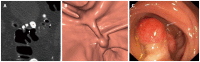

Twenty years after its introduction, computed tomographic colonography (CTC) has reached its maturity, and it can reasonably be considered the best radiological diagnostic test for imaging colorectal cancer (CRC) and polyps. This examination technique is less invasive than colonoscopy (CS), easy to perform, and standardized. Reduced bowel preparation and colonic distention using carbon dioxide favor patient compliance. Widespread implementation of a new image reconstruction algorithm has minimized radiation exposure, and the use of dedicated software with enhanced views has enabled easier image interpretation. Integration in the routine workflow of a computer-aided detection algorithm reduces perceptual errors, particularly for small polyps. Consolidated evidence from the literature shows that the diagnostic performances for the detection of CRC and large polyps in symptomatic and asymptomatic individuals are similar to CS and are largely superior to barium enema, the latter of which should be strongly discouraged. Favorable data regarding CTC performance open the possibility for many different indications, some of which are already supported by evidence-based data: incomplete, failed, or unfeasible CS; symptomatic, elderly, and frail patients; and investigation of diverticular disease. Other indications are still being debated and, thus, are recommended only if CS is unfeasible: the use of CTC in CRC screening and in surveillance after surgery for CRC or polypectomy. In order for CTC to be used appropriately, contraindications such as acute abdominal conditions (diverticulitis or the acute phase of inflammatory bowel diseases) and surveillance in patients with a long-standing history of ulcerative colitis or Crohn's disease and in those with hereditary colonic syndromes should not be overlooked. This will maximize the benefits of the technique and minimize potential sources of frustration or disappointment for both referring clinicians and patients.